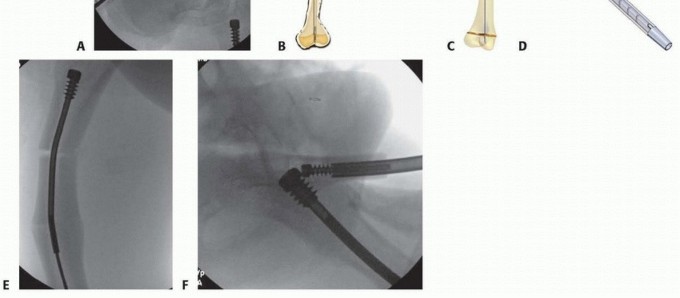

Revision

## When a rod system requires revision after maximal telescoping, it often can be retrieved through just a proximal incision.

## A guidewire is placed in the greater trochanter and into the cannulated portion of the female nail under fluoroscopic control.

## A reamer one size larger than the nail being removed is paced over the guidewire down to the top of the female nail.

## Specialized female and male retrievers, as shown, allow for intramedullary retrieval (TECH FIG 5A-D).

## Open osteotomy, cutting the rod and removing the segments, may be necessary to retrieve a broken or bent nail or one that has migrated laterally and distally. If the nail has overgrown into the bone, and open osteotomy can be performed, the rods cut,

P.574 P.575

and it can be removed. A Michele trephine can be used if necessary to enlarge the canal to allow the passage of the female nail head (TECH FIG 5E,F).

TECH FIG 5 • A. The female nail can usually be removed by passing a guidewire into the nail, reaming to the female nail, and using the revised, thinner, female nail extractor. This typically works even if the nail is somewhat bent. B. Female rod retriever. C. Male nail rod retriever. D. The male nail must be captured above the hole in the male nail extractor prior to turning the torque head of the male nail extractor in a counterclockwise direction. E. Severely bent nail with female nail overgrown into femoral canal. F. Open osteotomy, rods cut, Michele trephine used to enlarge canal to allow passage of nail distally. (B-D: Courtesy of Pega Medical, Inc., Montreal, Canada.)